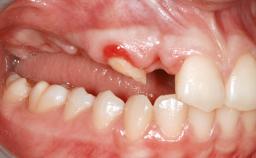

Guided Bone Regeneration (GBR) with a Particulated Autologous Graft and a ePTFE-Reinforced Membrane for Vertical Augmentation of a Single-Tooth Edentulous Space in the Esthetic Zone

A 47-year-old Caucasian woman with a single-tooth edentulous space at the site of the left maxillary canine was referred for treatment. She had undergone traumatic extraction of this impacted canine several months before referral. Her chief complaint was the dissatisfying appearance of her smile. The patient desired a stable and esthetic rehabilitation of the site. Her dental history showed no evidence of periodontal disease or bruxism. She had no systemic diseases, was not taking any medications, and did not smoke. The extraoral examination revealed a high lip line and an inadequate soft-tissue volume at the defective canine site. Large black triangles were visible between the canine and its adjacent teeth.

Soft Tissue Anatomy Intact Defective

Bone Volume Horizontally and vertically sufficient Horizontally deficient Deficient vertically or deficient vertically AND horizontally